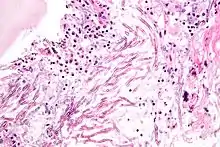

Aspergillosis. H&E stain.

The most common pathogenic species are Aspergillus fumigatus and Aspergillus flavus. Aspergillus flavus produces aflatoxin which is both a toxin and a carcinogen and which can potentially contaminate foods such as nuts. Aspergillus fumigatus and Aspergillus clavatus can cause allergic disease. Some Aspergillus species cause disease on grain crops, especially maize, and synthesize mycotoxins including aflatoxin. Aspergillosis is the group of diseases caused by Aspergillus. The symptoms include fever, cough, chest pain or breathlessness. Usually, only patients with weakened immune systems or with other lung conditions are susceptible.[1]

The spores of Aspergillus fumigatus are ubiquitous in the atmosphere. A. fumigatus is an opportunistic pathogen. It can cause potentially lethal invasive infection in immunocompromised individuals.[10] A. fumigatus has a fully functional sexual cycle that produces cleistothecia and ascospores.